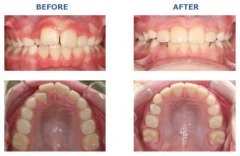

成功的美容修复怎么辨别?

美容修复能够快速矫正成人畸形牙、色素牙问题,因而受到万千美牙者的青睐,...【详细】